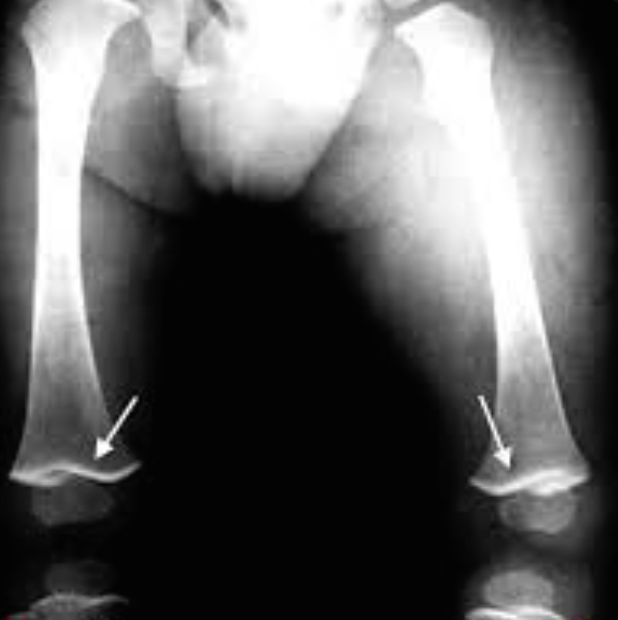

Lead poisoning lead line in end femur.